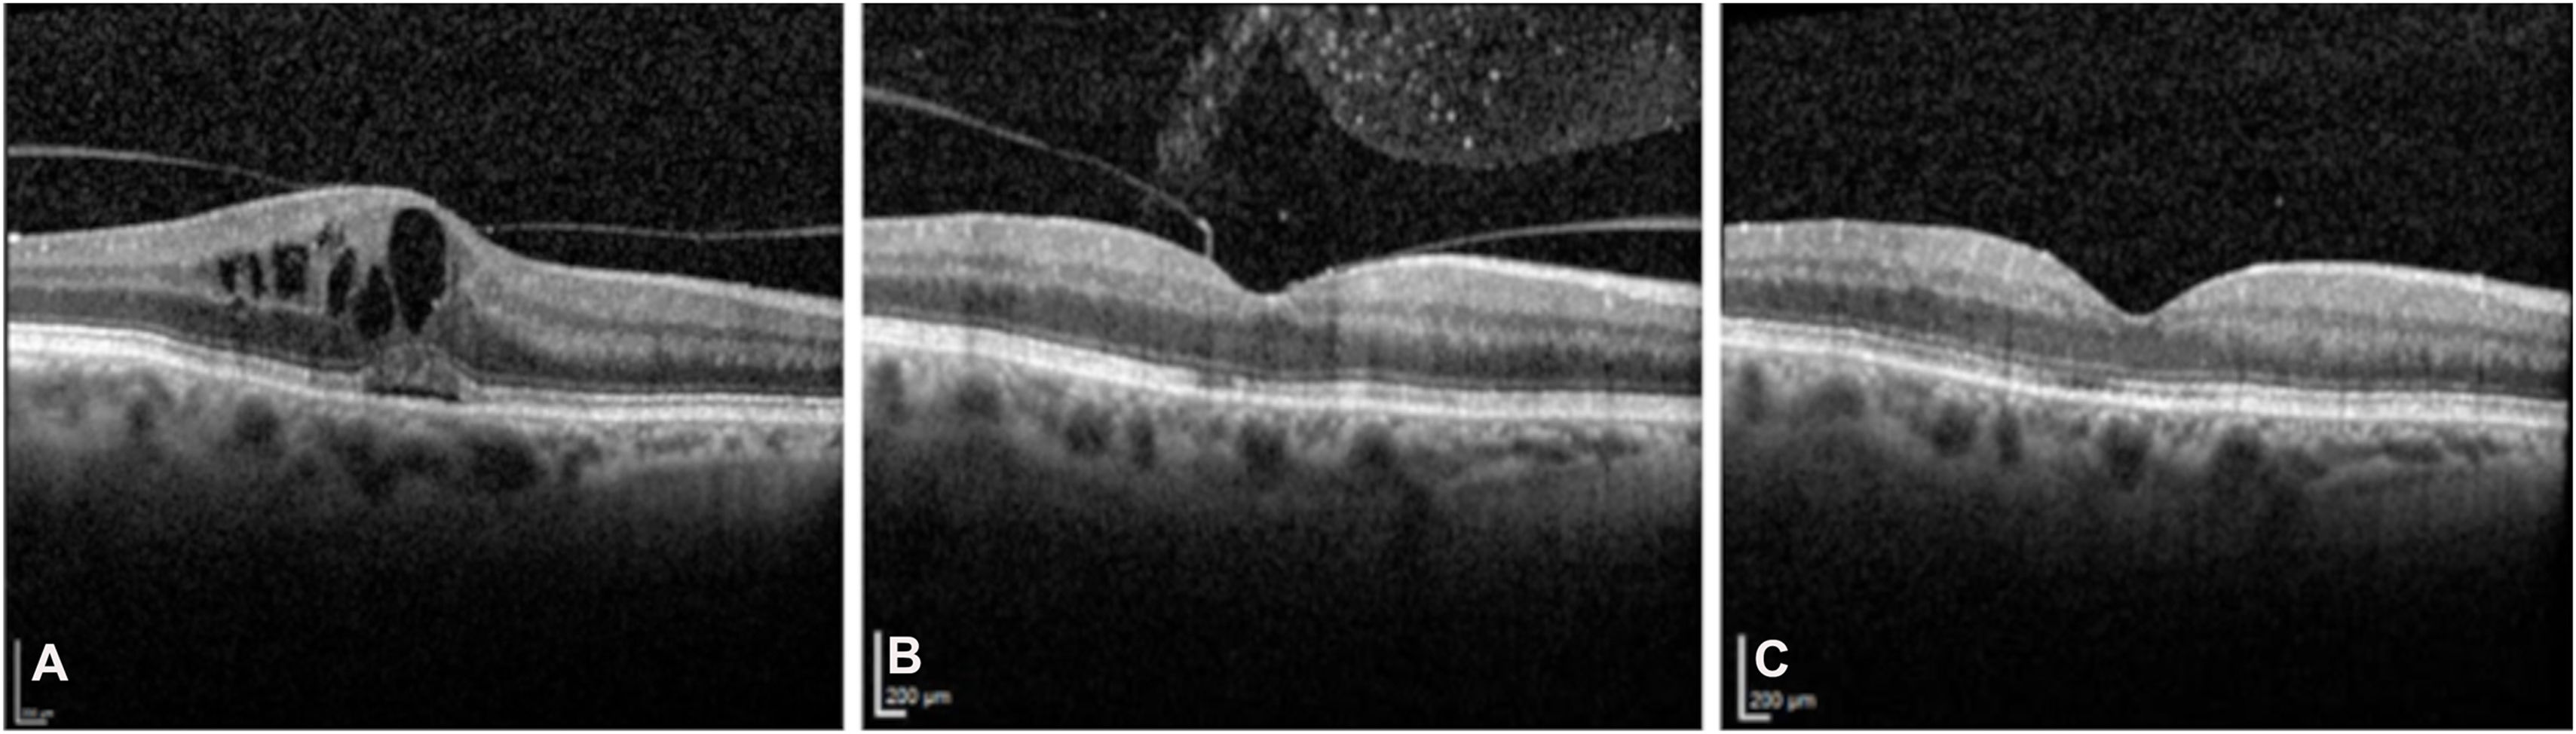

La angiofluoresceinografía mostró árbol vascular normal, sin áreas de hipoperfusión ni fugas. La tomografía de coherencia óptica evidenció resolución del edema macular y aclaramiento progresivo de puntos hiperreflectivos en vítreo posterior (figs. 3 y 4). La agudeza visual se recuperó a 0.7 logMAR, correspondiente a su nivel visual habitual.

Tomografía de coherencia óptica con evolución temporal del perfil macular y del vítreo posterior. A) Preinyección: engrosamiento retiniano con edema macular quístico, leve desprendimiento subfoveal y hialoides posterior parcialmente adherida. B) Fase aguda (día 10 postinyección): resolución de espacios cistoideos y ocupación del vítreo posterior por densidades hiperreflectivas. C) Fase resolutiva (día 30 postinyección): recuperación completa del perfil foveal y aclaramiento del espacio vítreo.